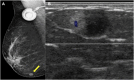

Breast metastases from extramammary cancers are rare and usually related to poor prognosis. The extramammary tumours most frequently exhibiting breast metastases are melanoma, lymphomas, ovarian cancer, lung and neuroendocrine tumours, and sarcomas. Owing to the lack of reliable and specific clinical or radiological signs for the diagnosis of breast metastases, a combination of techniques is needed to differentiate these lesions from primary breast carcinoma or even benign breast lesions. Multiple imaging methods may be used to evaluate these patients, including mammography, ultrasound, MRI, CT and positron emission tomography CT. Clinical and imaging manifestations are varied, depend on the form of dissemination of the disease and may mimic primary benign and malignant breast lesions. Haematologically disseminated metastases often develop as a circumscribed mass, whereas lymphatic dissemination often presents as diffuse breast oedema and skin thickening. Unlike primary carcinomas, breast metastases generally do not have spiculated margins, skin or nipple retraction. Microlobulated or indistinct margins may be present in some cases. Although calcifications are not frequently present in metastatic lesions, they occur more commonly in patients with ovarian cancer. Although rare, secondary malignant neoplasms should be considered in the differential diagnosis of breast lesions, in the appropriate clinical setting. Knowledge of the most common imaging features can help to provide the correct diagnosis and adequate therapeutic planning.